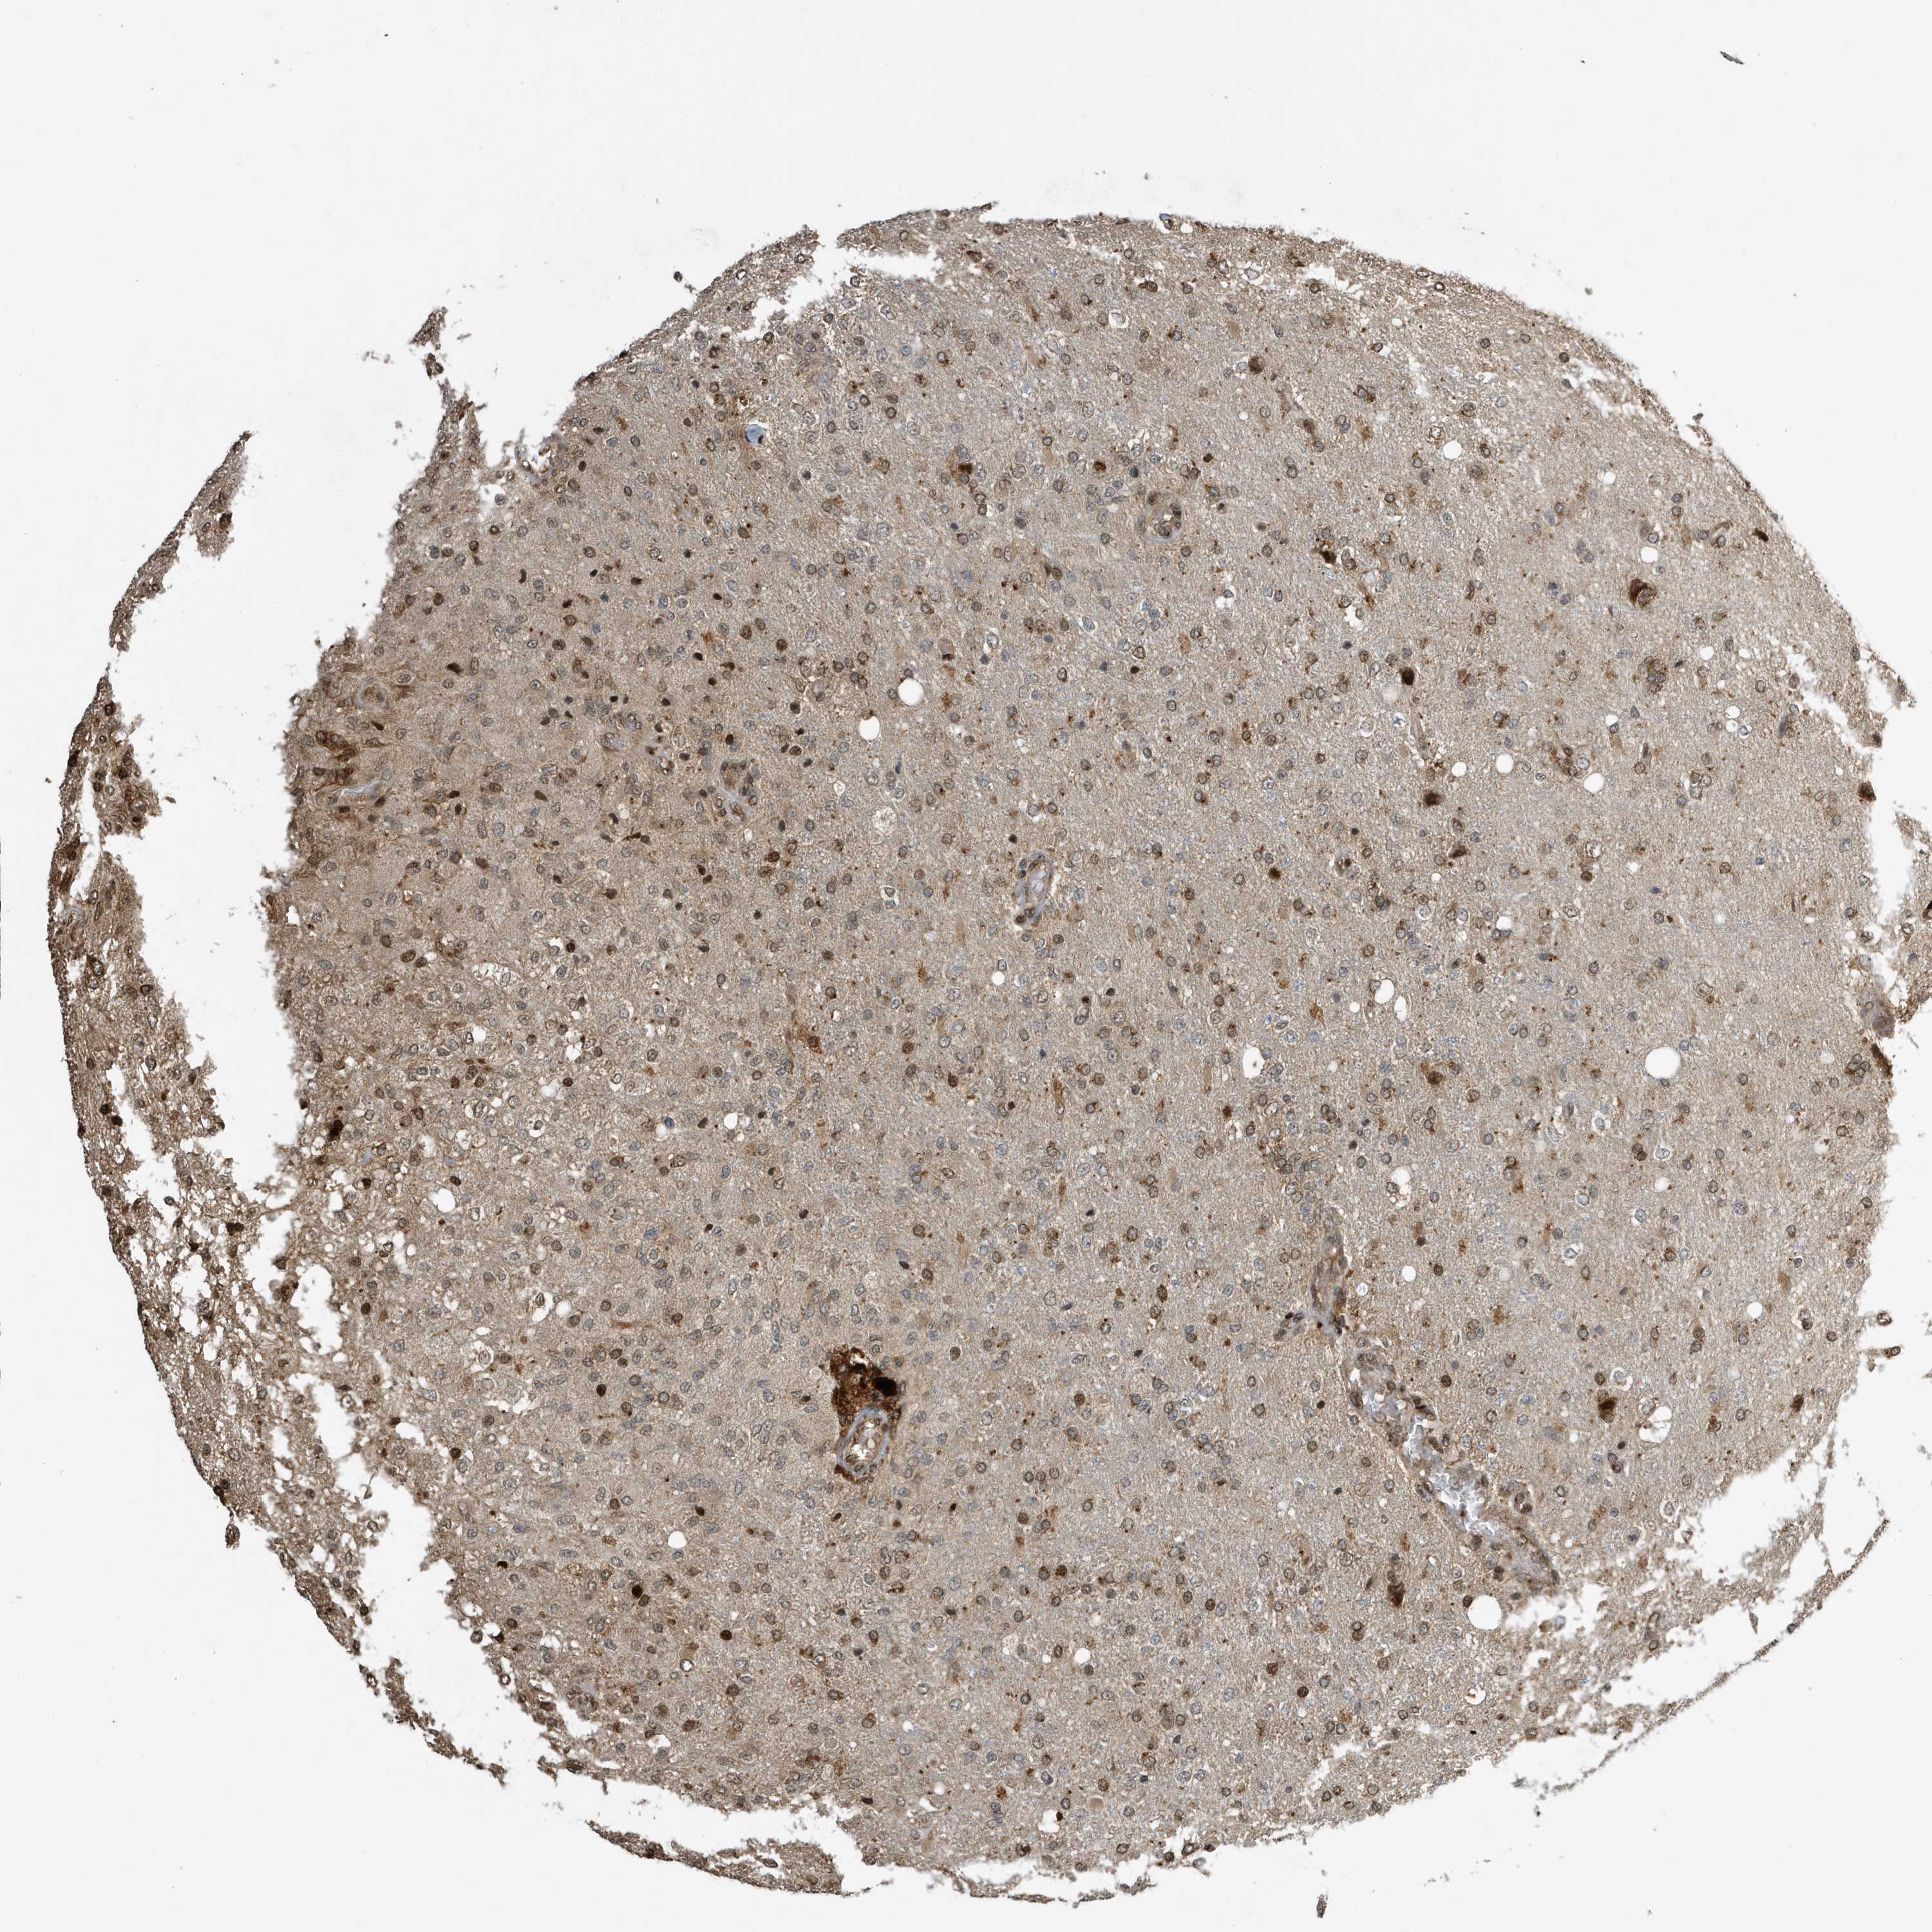

GLIOMA - Protein expressioni

A mouse-over function shows sample information and annotation data. Click on an image to view it in a full screen mode. Samples can be filtered based on level of antibody staining by selecting one or several of the following categories: high, medium, low and not detected. The assay and annotation is described here.

Note that samples used for immunohistochemistry by the Human Protein Atlas do not correspond to samples in the TCGA dataset.

Antibody stainingi

Antibody staining in the annotated cell types in the current human tissue is reported as not detected, low, medium, or high, based on conventional immunohistochemistry profiling in selected tissues. This score is based on the combination of the staining intensity and fraction of stained cells.

Each image is clickable and will lead to virtual microscopy that enables deeper exploration of all samples and also displays staining intensity scores, fraction scores and subcellular localization as well as patient and tissue information for each sample.

Antibody CAB034070

Staining

High

Medium

Low

Not detected

Intensity

Strong

Moderate

Weak

Negative

Quantity

>75%

75%-25%

<25%

None

Location

Nuclear

Cytoplasmic/membranous

Cytoplasmic/membranous,nuclear

Glioma, malignant, High grade

Glioma, malignant, Low grade